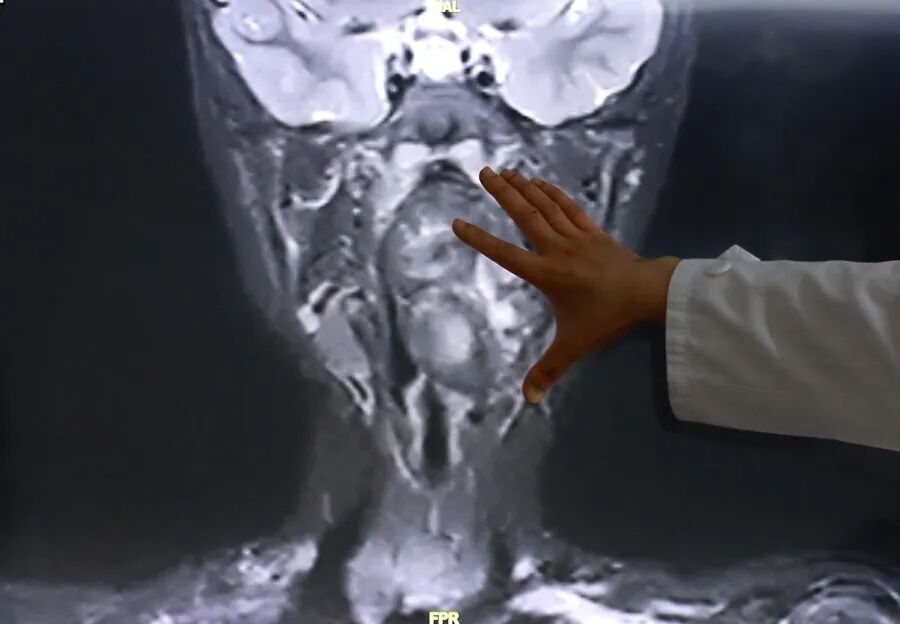

接诊后,综合前期检查及患儿家长自述病情,复旦儿科专家团队高度重视气道梗阻风险,立即启动复杂气道疾病绿色通道,完善增强CT及磁共振检查,明确小亮所患的肿瘤约7×3.5×3厘米,犹如“拳头”般大小。

专家表示,该肿瘤紧邻颈内动静脉并将血管明显向外推移,肿瘤向咽喉腔内隆起,占据大部分口咽及下咽腔,严重压迫声门,随时可能发生窒息。

“6岁男孩的口咽腔大概在8公分左右,这个孩子的肿瘤已经高达6公分多,整个气道已经完全被这个膨大的肿瘤占据了,只有一条黑颜色的线,这是它透气的空间,再让它继续膨胀下来,它首先出现的一个症状应该是呼吸道的梗阻窒息,会出现窒息致死的可能。”陈超说。